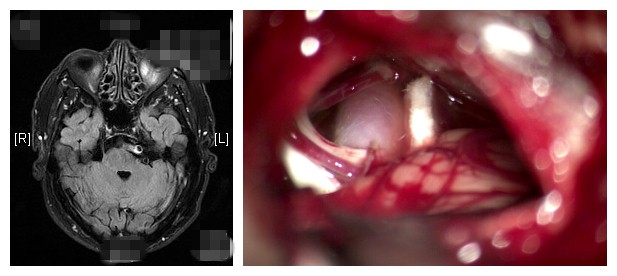

3月初,朱大爷来到了北京清华长庚医院神经外科就诊,经磁共振检查发现,患者基底动脉压迫了左侧三叉神经根。结合患者的病情,王劲教授建议行微创的“三叉神经根显微血管减压术”,根治疼痛。22日,由王劲主刀,从耳后手术在颅骨上打开一元硬币大小的骨窗,打开硬脑膜,在显微镜下查找导致病变的“责任血管”,“多为动脉,如小脑上动脉、小脑下前动脉、基底动脉都可能造成神经压迫”王劲说。术中将血管游离开,再将特氟龙绵片置于脑干和血管之间,把血管垫开,避免压迫神经根,这是止痛的关键步骤。缝合硬脑膜后,用钛网补上颅骨,缝合切口,手术顺利结束,全程两小时左右,出血少。术后,效果立竿见影,“脸一点也不疼了”,朱大爷高兴地说。

图为三叉神经痛患者的核磁及术中影像

三叉神经根显微血管减压术,正是通过手术把产生压迫的血管和三叉神经根分开,从而根治三叉神经痛。(编辑 韩冬野)